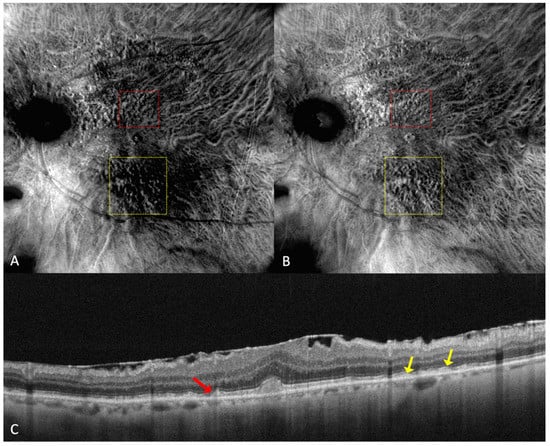

Figure 4.

(A) On the retromode image DR dot SDDs are round, hyporeflective lesions, and ribbon SDDs are difficult to see. (B) Retromode image DL shows each dot SDD as “hyporeflective core” with a “hyperreflective halo” [24], while the ribbon SDDs tend to have a reticular structure. (C) SD-OCT shows dot SDD (red arrow), ribbon SDDs (yellow arrows), and also a hyper-reflective layer on the retinal surface.

Parravano et al. conducted a study on reticular pseudodrusen imaging. Considering the characteristics of the lesions by their aspect on retromode images, the deposits were classified as round, bended, or interlacing [31].

Cozzi et al. investigated the accuracy of different retinal-imaging modalities in AMD patients. The study found that dot SDDs are hard to detect with retromode because of their high resemblance to small drusen, so the method’s accuracy is reduced in both DR (64.6% sensitivity; 85.7% specificity) and DL (76.6% sensitivity; 83.3% specificity), in comparison to other investigations [24]. The authors also specified that the DR or DL modes might not be able to detect ribbon SDDs due to their small size [24].

Dot SDDs in the retromode DR mode appear as pseudo3D round, hyporeflective lesions, and in the DL mode, they appear to have a target aspect—a hyperreflective halo surrounding a hyporeflective center. Ribbon SDDs are hardly detectable in the retromode illumination DR, and in the DL mode, they have a “reticular pattern” [24].